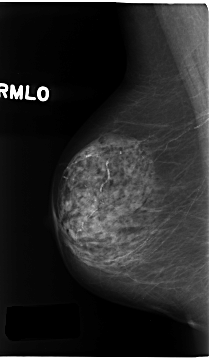

C_0196_1.RIGHT_MLO

RIGHT_CC LINES 4616 PIXELS_PER_LINE 2824 BITS_PER_PIXEL 12 RESOLUTION 50 NON_OVERLAY

RIGHT_MLO LINES 4672 PIXELS_PER_LINE 2712 BITS_PER_PIXEL 12 RESOLUTION 50 NON_OVERLAY